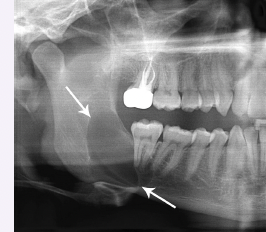

Cleidocranial dysplasia

● Delayed closure of frontal sutures and impaired osteoblast differentiation

● Characterized by hypoplastic or absent clavicles, prominent skull, mandibular prognathism, and

hypertelorism

● Associated with supernumerary teeth, prolonged retention of primary teeth, and cleft palate